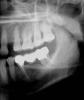

nina50 Опубликовано 2 августа, 2013 Поделиться Опубликовано 2 августа, 2013 (изменено) Уважаемые врачи, очень нужна ваша консультация!Ситуация такова: нахожусь на обследовании перед постановкой в очередь на трансплантацию органа. Нри этом необходимо получить согласие стоматолога, Он должен удостовериться и заверить своей подписью, что состояние зубов не представляет угрозы для здоровья реципиента (то есть меня) и что все источники инфекции в ротовой полости санированы.Врач частной стом.клиники, где я лечусь, такаю бумагу подписал. Врачу госуд. стоматологии при университетской больнице не нравится состояние обного зуба - 47. Этот зуб опорный для моста 45-47. Кони его действительно не пройдены и десна около иногда слегка воспаляется. Мы с моим стоматологом знали об этом, и он собирался, сняв мостик, прерлечить семерку и поставить новый мост.Но стоматолог из больничной клиники категорически настаивает на удалении семерки. Вроде видит воспаление вокруг корня. Очень не хочется удалять зуб, ибо это потеря жевательной функции с правой стороны! А с левой - тоже жевание затруднено: нет 27, 25 - имплантат, берегу его, не нагружаю.Что делать? Посмотрите пожалуйста снимок - можно пойти на риск, перелечить корни? Или уж удалить - но можно ли поставить имплантаты 46-47? Там вроде кость сильно ушла, очень сомневаюсь, что имплататы найдут. за что зацепиться... Три варианта решения. из которых первый совсем не нравится...Решать надо быстро.В понедельник записалась к своему стоматологу в частной клинике, попробуем обсудить. Но хотелось бы предваритьельно почитать о вашем коллективном мнении.Спасибо заранее и всего доброго!Прошу прожения, если фото не совсем четкие, делала, как умею. На месте24 сейчас тоже имплантат с коронкой. Изменено 2 августа, 2013 пользователем nina50 Ссылка на комментарий

Bier Опубликовано 5 августа, 2013 Поделиться Опубликовано 5 августа, 2013 На фоне приема бисфосфонатов, вам таки показано нехирургическое лечение! Ваш стоматолог может об этом и не знать, не так давно появилась эта информация. Так что найдите эндодонтиста с микроскопом и лечите свой зуб. По плоскому снимку невозможно оценить толщину кости и нельзя сказать можно ли без пластики поставить имплантат. Но на фоне приема бисфосфонатов - нельзя. 2 Ссылка на комментарий